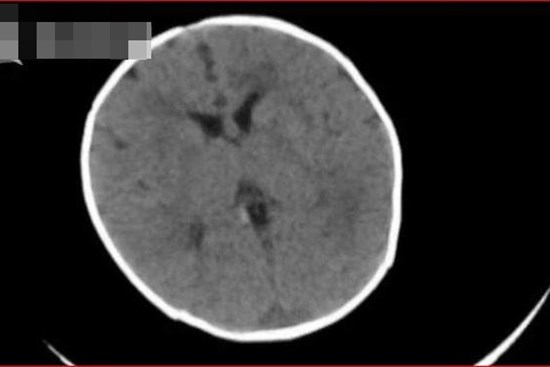

Đột quỵ do xuất huyết não rất nguy hiểm gây nguy cơ tàn phế và tỷ lệ tử vong cao. Thời gian gần đây, Bệnh viện Đa khoa tỉnh Quảng Ninh tiếp nhận số lượng bệnh nhân tai biến mạch máu não tăng đột biến.

Xuất huyết não thường diễn ra âm thầm, đến khi phát bệnh thì lại rất nghiêm trọng bởi dấu hiệu của nó không khác gì đau đầu thông thường.